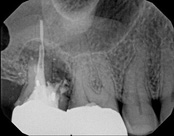

The patient presented with mild pain, a cavity, and a broken filling was evident. After performing diagnostic testing, the diagnosis was: irreversible pulpitis, symptomatic periradicular periodontitis. Root canal therapy was done and the tooth healed well and is still functioning.